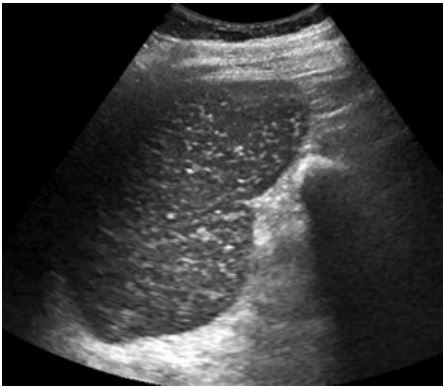

Homem de 68 anos refere diversos episódios prévios de hemorragia digestiva alta por varizes esofágicas. Conta ter tratado esquistossomose há muito tempo. Diz que o seu baço é grande há vários anos. Na ultrassonografia de abdome, foram evidenciadas imagens no parênquima esplênico (foto). A que correspondem essas imagens?